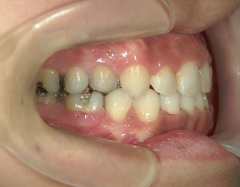

矯正歯科 治療前 上顎を装置(QH)で拡大後ワイヤー矯正へ移行、右下5番左下4番 計2本抜歯叢生改善

no.28_6958_治療前_右.jpgno.28_6958_治療前_正面.jpgno.28_6958_治療前_左.jpg